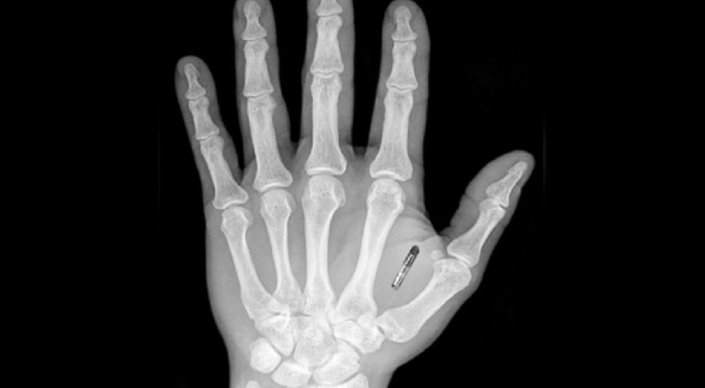

Әлем • 25 Шілде, 2017

Әлемде компаниялар қызметкерлеріне микрочип ендіруде

Америкалық Three Square Market пен шведтік Epicenter компаниялары қызметкерлерінің қолына микрочиптер ендірген.